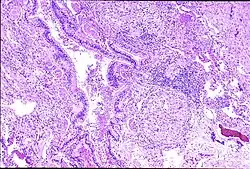

Peribronchal non-necrotizing granuloma from berylliosis

Granuloma formation is seen in other diseases such as tuberculosis and sarcoidosis. Sarcoidosis, like berylliosis, also produces granulomas without a necrotic core, and so distinction between the two processes can be difficult.

In susceptible persons, beryllium exposure can lead to a cell-mediated immune response. The T-cells become sensitized to beryllium. Each subsequent exposure leads to an immune response involving CD4+ helper T-lymphocytes and macrophages accumulating in the lungs. As this response continues macrophages, CD4+ T-lymphocytes and plasma cells aggregate together to form the noncaseating granulomas.[6][7] When beryllium is phagocytized by macrophages, the beryllium triggers macrophage apoptosis, thereby reducing beryllium clearance from the lungs and eventually resulting in secondary necrosis and lysis.[8] Eventually, the outcome is fibrosis of the lung.[9][10]